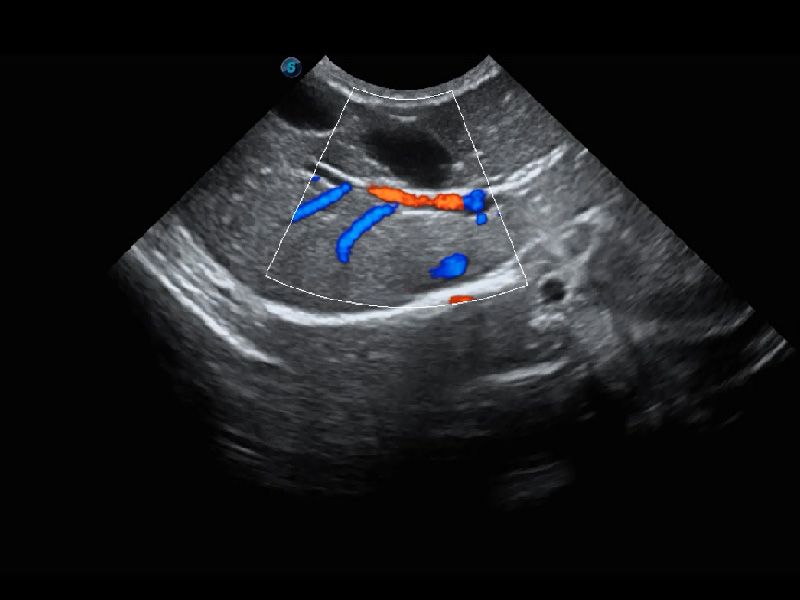

ProPet 60 作为一款高端台式动物超声设备,为动物医生的日常诊断提供了一系列贴合动物临床需求、解决临床实际问题的高级成像功能。凭借全系列高清探头,满足医生对腹部、心脏、生殖、浅表、肌骨等成像的所有需求,切实帮助您提升检查效率,提高诊断信心。

动物是人类最亲密的朋友和最值得信赖的伙伴。米兰官方网站也一直致力于探索动物专用的超声影像解决方案。 全新推出的ProPet系列,是米兰官方网站在动物超声影像智能化、专业化、精准化的一次跨越式革新。动物不能用言语来表述自己的不适,通过超声影像,ProPet系列搭建了动物医生与不同物种沟通的“桥梁”,为动物医生注入了“治愈之力”。